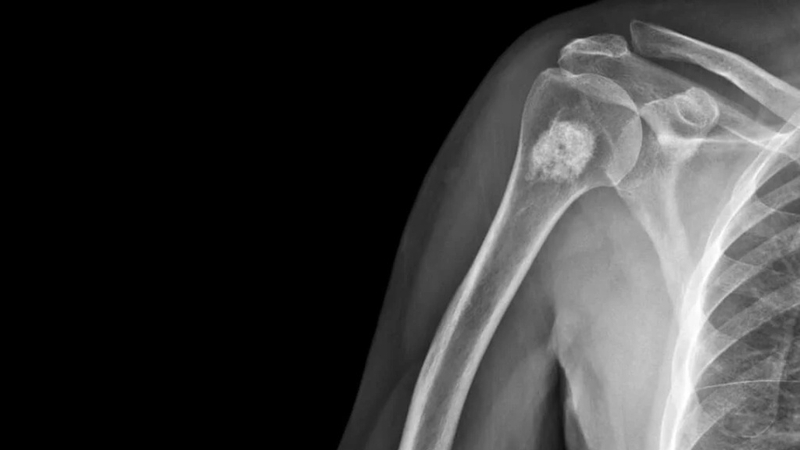

U sụn xương ở trẻ em là sự tăng sinh quá mức của xương và sụn. Các khối u này có thể xuất hiện ở bất kỳ vị trí nào, đặc biệt thường gặp ở gần các đầu xương như xương cánh tay, xương đùi, xương chày và các xương cẳng tay. Bên cạnh đó, một số vùng xương phẳng như xương bả vai và xương chậu cũng có khả năng bị ảnh hưởng. Đa số các khối u sụn xương đều là khối u lành tính, thường xuất hiện trong quá trình phát triển của hệ xương tức ở độ tuổi từ 10 - 25 tuổi.

Ngoài việc thực hiện các cuộc kiểm tra lâm sàng và tìm hiểu về lịch sử bệnh lý của người bệnh, các bác sĩ có thể sẽ chỉ định thực hiện một số xét nghiệm để xác định chẩn đoán chính xác như: